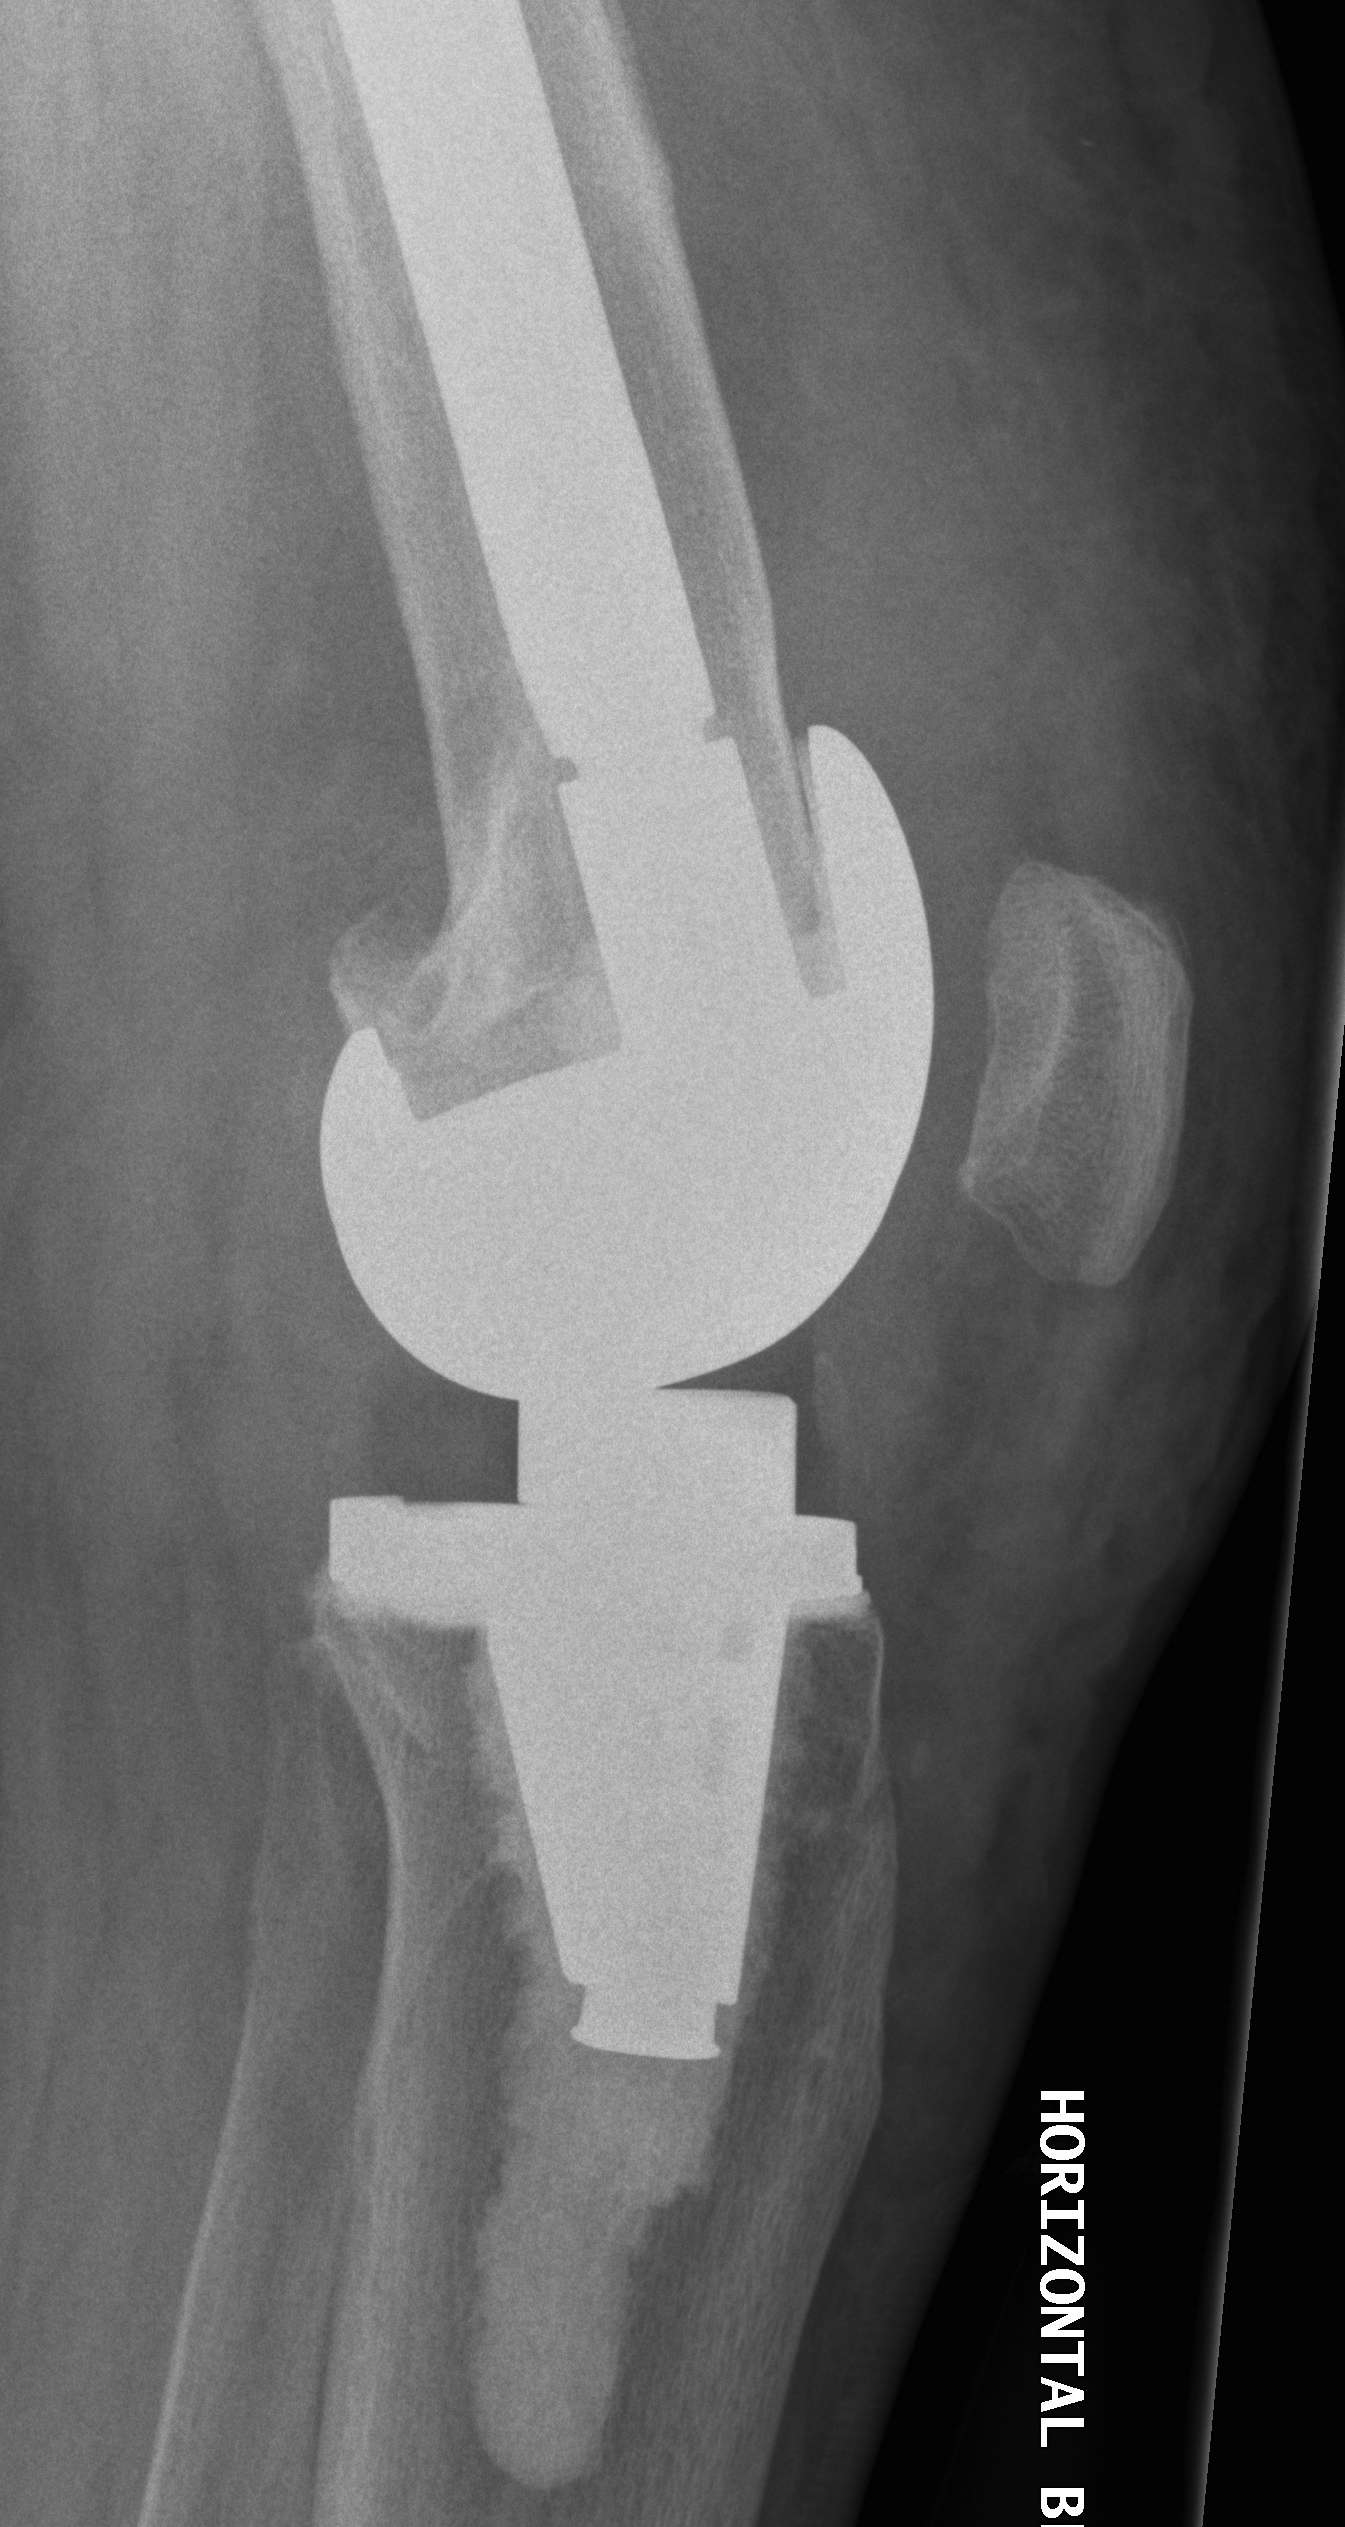

- 184 cemented revision TKR with press fit stems

- significant bone loss

10. Loosening